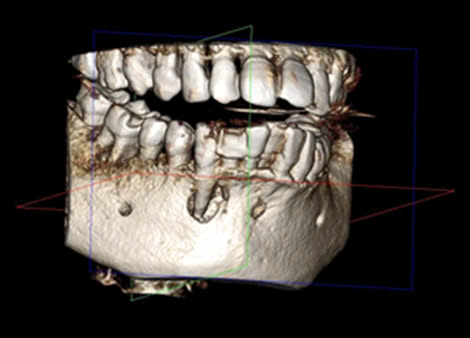

Hình 1. CBCT trước điều trị, bệnh nhân Đ.Q.Q